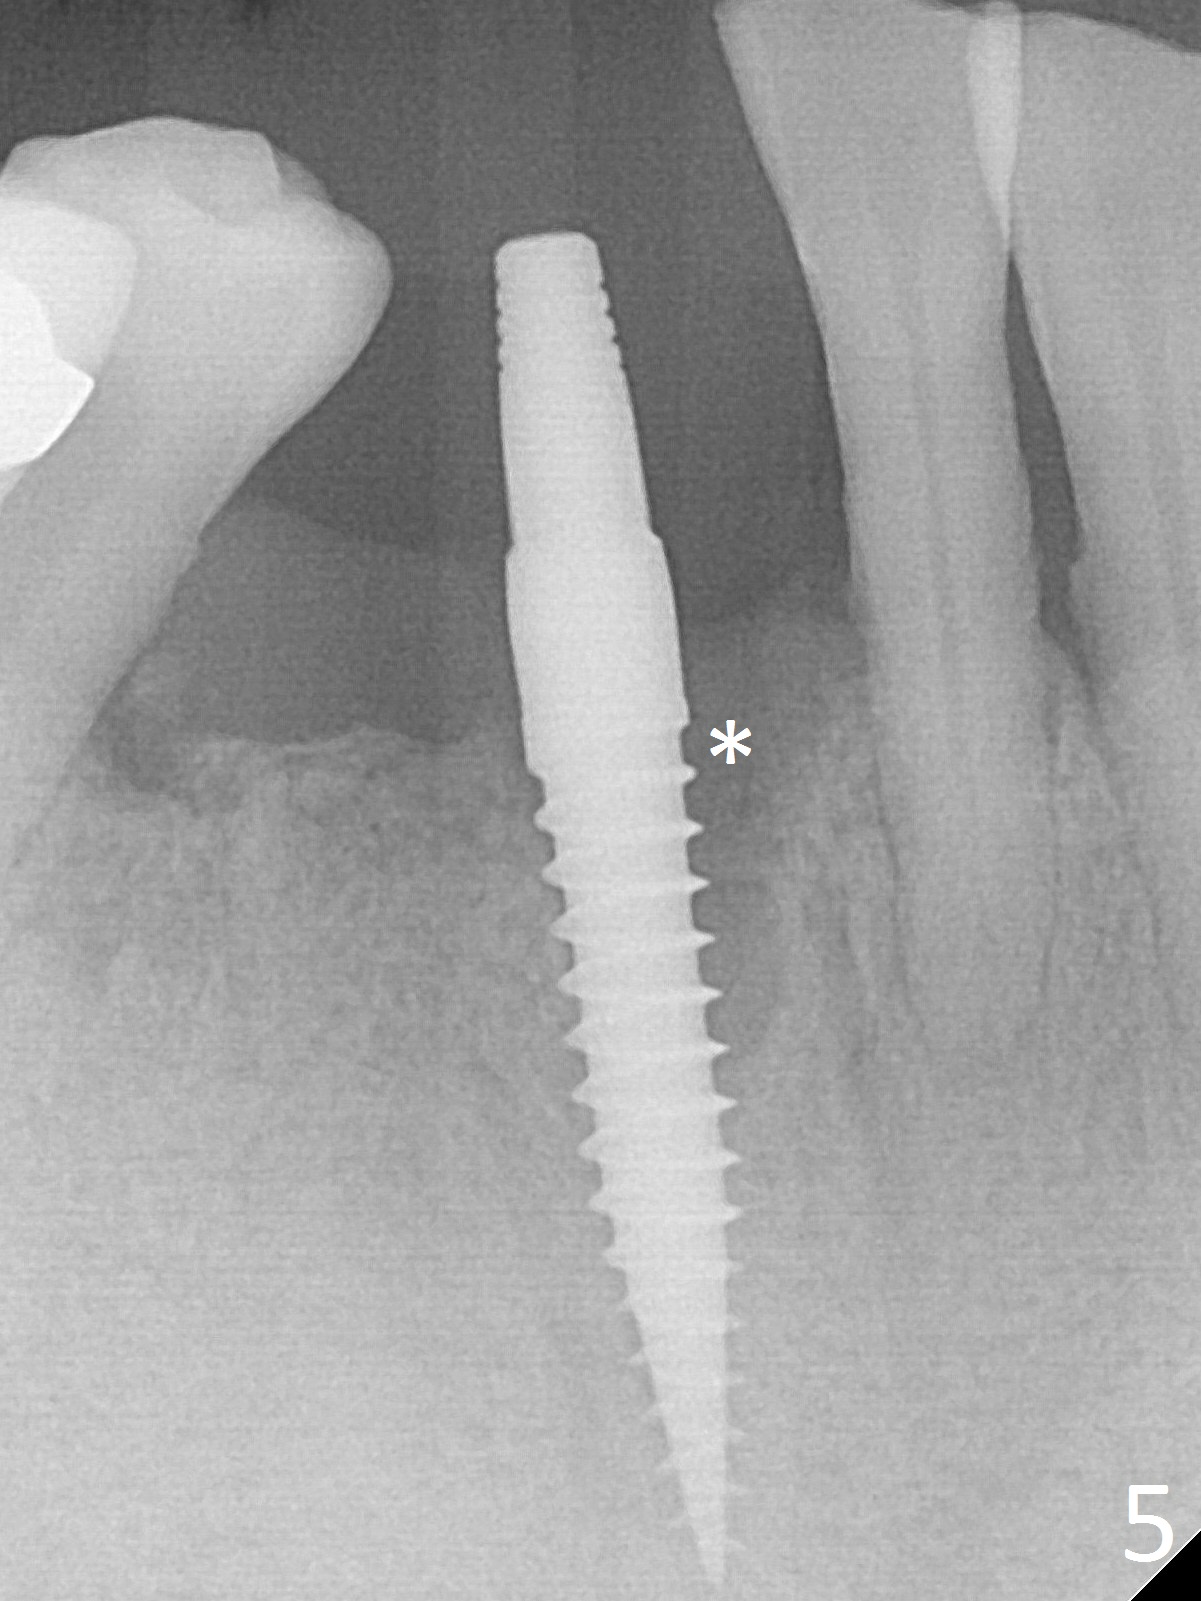

The lower dentition is special, consisting of a residual root (Fig.1 ^), 2 incisor (I), 1 canine (C), 1 premolar (P) and 1 molar (M). The residual root looks like an incisor with rotation of 90º (Fig.2,3). Osteotomy is initiated (Fig.4) for a 3x16(2) mm 1-piece implant (Fig.5 with 45 Ncm). The implant is being placed as distal as possible (Fig.4 arrow) so that a large canine-like provisional is to be fabricated in the large edentulous space (Fig.8,9) after bone graft (Fig.6,7 *). The gingiva around the provisional (Fig.10 P) remains healthy 11 days postop with occlusal clearance against the opposing dentition (Fig.11). The implant threads are not exposed with the help of bone graft 3 months 1 week postop (Fig.12). The gingiva around the implant is healthy (Fig.13). Soft tissue socket is formed by the provisional (Fig.14 *).